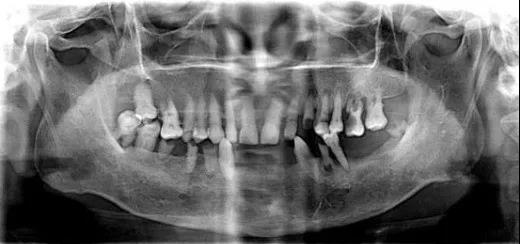

▲ 常见的牙片是二维的

种植医生可以从任意角度观察分析病例,如缺牙区牙槽骨吸收程度、余留牙是否有炎症等需要先进行治疗以避免干扰种植手术的问题。

马先生的牙齿情况